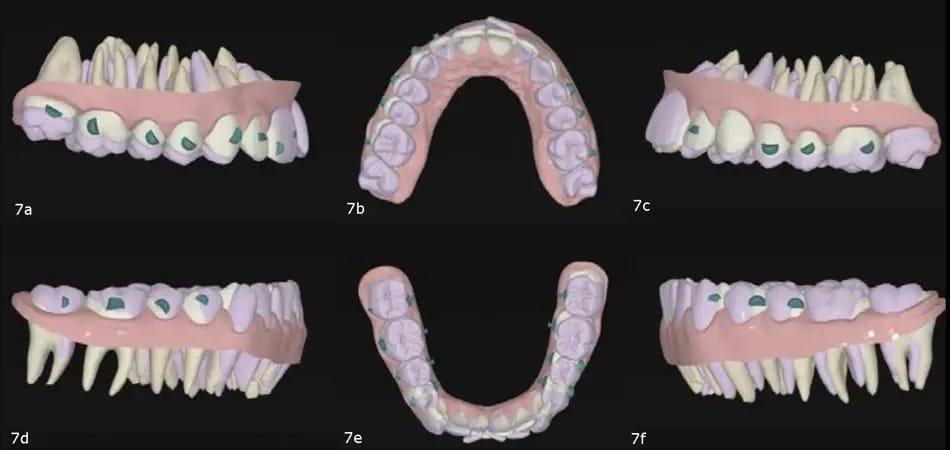

Используя программное обеспечение для планирования лечения, удалось смоделировать выравнивание обеих дуг (без выпячивания резцов), расширение верхней челюсти, проникновение сзади как в верхней, так и в нижней челюсти, коррекцию средней линии нижней челюсти и, в конечном счете, авторотацию нижней челюсти. Для устранения скученности зубов на нижней челюсти без дальнейшего удлинения зубов была применения техника задней интерпроксимальной редукции IPR (фото 7).

Фото 7a–f: 3D наложение запланированных движений.